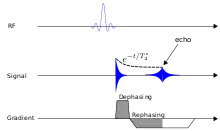

Gradient echo

A gradient echo sequence does not use a 180 degrees RF pulse to make the spins of particles coherent. Instead, it uses magnetic gradients to manipulate the spins, allowing the spins to dephase and rephase when required. After an excitation pulse, the spins are dephased, no signal is produced because the spins are not coherent. When the spins are rephased, they become coherent, and thus signal (or "echo") is generated to form images. Unlike spin echo, gradient echo does not need to wait for transverse magnetisation to decay completely before initiating another sequence, thus it requires very short repetition times (TR), and therefore to acquire images in a short time. After echo is formed, some transverse magnetisations remains. Manipulating gradients during this time will produce images with different contrast. There are three main methods of manipulating contrast at this stage, namely steady-state free-precession (SSFP) that does not spoil the remaining transverse magnetisation, but attempts to recover them (thus producing T2-weighted images); the sequence with spoiler gradient that averages the transverse magnetisations (thus producing mixed T1 and T2-weighted images), and RF spoiler that vary the phases of RF pulse to eliminates the transverse magnetisation, thus producing pure T1-weighted images.[39]

For comparison purposes, the repetition time of a gradient echo sequence is of the order of 3 milliseconds, versus about 30 ms of a spin echo sequence.